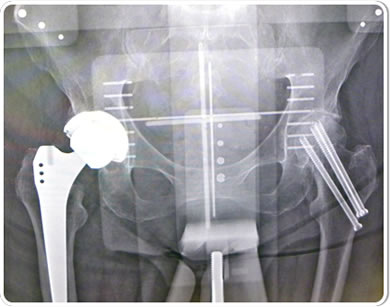

This 84 year old frail, 3 packs-per-day smoker previously sustained two hip fractures in minor falls due to her severe osteoporosis. Her left hip was pinned five years ago and healed uneventfully, but she subsequently developed post-traumatic arthritis that is now quite disabling.

A K2 mid-length stem was selected as an ideal choice in converting her to a total hip arthroplasty for three reasons. First, her prior fracture had compacted down as it healed, leaving her with a shortened offset and valgus neck that are better re-approximated with a modular prosthesis. Second, most modular primary systems do not provide extra length options, which was helpful in this particular case in bypassing the stress riser of her previous pin sites as well as strengthening the proximal one-third femur in this osteoporotic patient who has already demonstrated multiple fragility fractures and lessening her chance of a periprosthetic fracture in the future. Third, the simplicity of the K2 system allowed this case to be completed in about half an hour, whereas many modular systems (such as traditional S-ROM) require more preparation and operating time for milling out the proximal femur, etc. The Zweymueller geometry allowed a quick and rotationally solid fit in the osteoporotic bone. The patient was able to ambulate in the hallway that evening and confidently place full weight on the solidly seated stem.